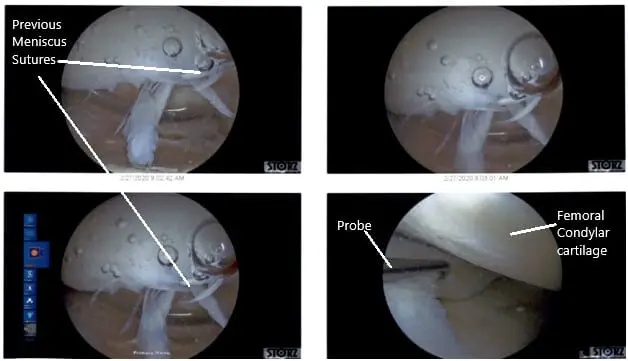

Examination of the knee showed grade 3 to grade 4 arthritis of the trochlea, grade 2 to grade 3 arthritis of the lateral facet of the patella, grade 2 to grade 3 arthritis of the medial femoral condyle, previous repair of the medial meniscus because of the sutures as well as long tear of the meniscocapsular junction of the medial meniscus of the left knee.

Intraoperative Arthroscopic Views of the left knee.

There were some medial margin tearing and fraying of the lateral meniscus which was taken care of with the shaver and meniscectomy performed to stable margins. The ACL (history of ACL reconstruction) showed fraying in the intertrochlear notch, but the ACL was intact.